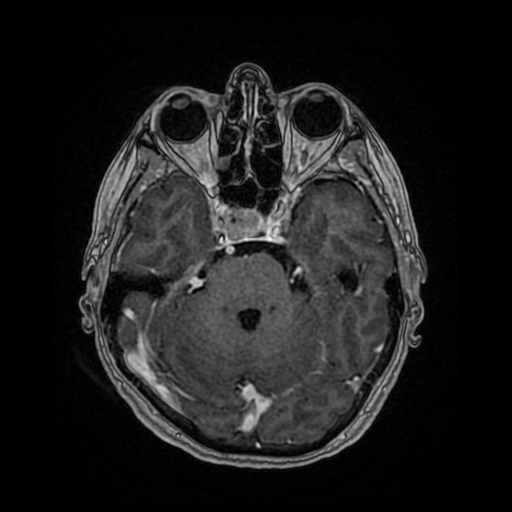

W badaniu CT widoczne jest rozległe krwawienie dokomorowe.

W badaniu angiografii subtrakcyjnej widoczne jest rozległe (ponad 3 cm) gniazdo naczyniowe zaopatrywane z tętnicy przedniej mózgu prawej, zarówno z gałęzi okołospoidołowej, która oddawała 2 tętnice żywiące, jak i gałęzi korowych, oddając jedno naczynie żylne drenujące do zatoki strzałkowej górnej.

W tym przypadku chora została zakwalifikowana do leczenia operacyjnego – kraniotomii czołowej przystrzałkowej i resekcji zmiany naczyniowej. Zmiana została usunięta, bez nowych deficytów neurologicznych. W kontrolnym badaniu DSA nie uwidoczniono resztkowej przetoki naczyniowej, co jest sukcesem operacyjnym.